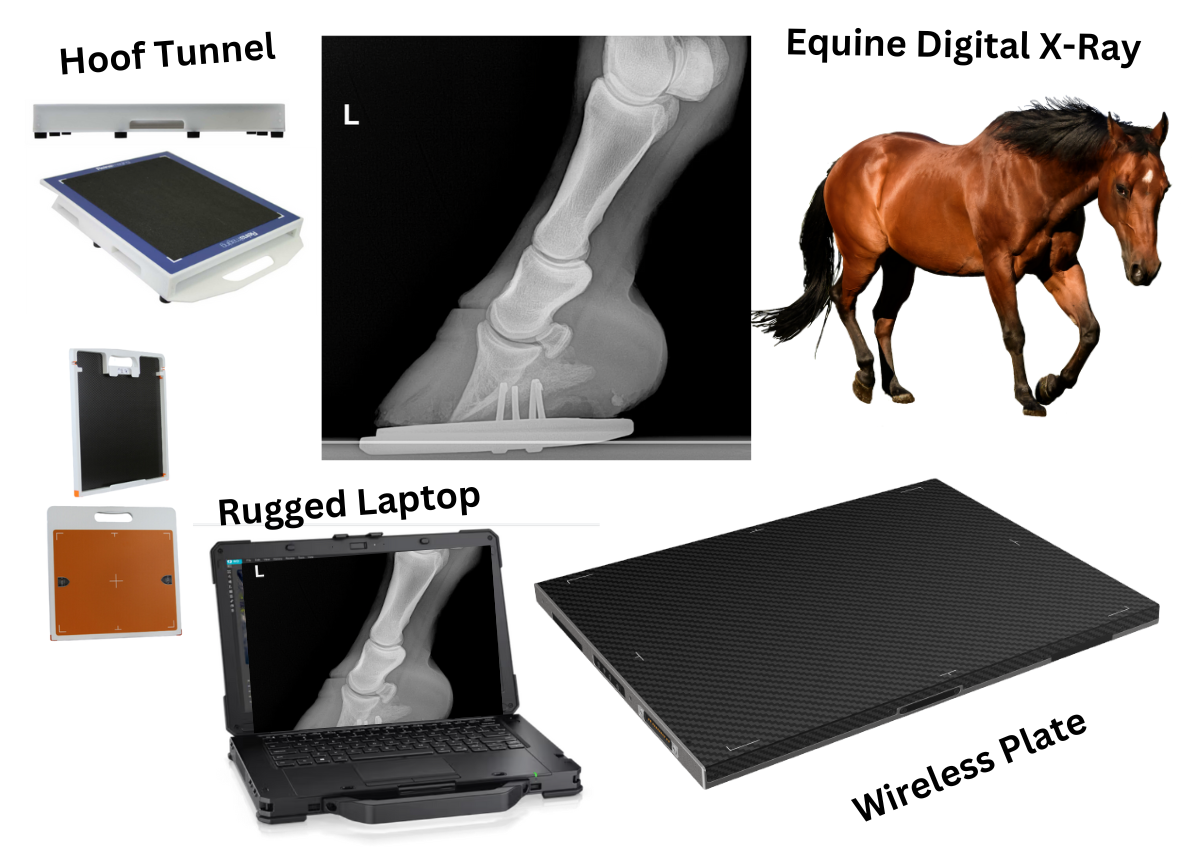

10” x 12” 100 Micron/UM Wireless Digital X-ray

Equine Detector with Computer/ Software $28,995 / $495 mo.

Free Legs and Hooves Generator INCLUDED! A $6000 value!

10x12" Image Area Detector Equine Package with Flexible Non-glass Substrate 100um/micron Pixel Pitch (4.3lp/mm detector

Rugged Computer and case

Latitude 5430 Rugged Laptop

14" Non-touch Display,

Intel i% processor,

16GB RAM

512GB

SSD Memory

3-year warranty

Pelican case sized for detector and laptop

Panel Holder 10x12 PolyCarbon Grid Encasement With Single Handle

Equine Tunnel Included

Protect your DR panel from damage and keep it clean with the Equine Tunnel. This sturdy tunnel features rubber feet that keep the DR panel raised up off the floor, fully protected from dirt and debris.

Equine Tunnel